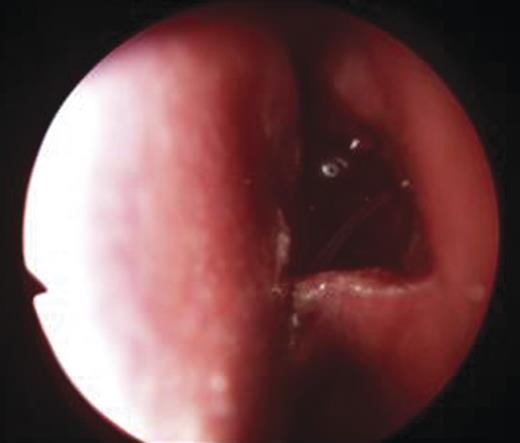

- An endoscopic left anterior ethmoidectomy was performed (Fig. 9) with marsupialisation of the mucocele (Fig. 9) and trimming of the DCR stent (Fig. 10)

Figure 9:Transnasal endoscopic left anterior ethmoidectomy and marsupialization of mucocele.